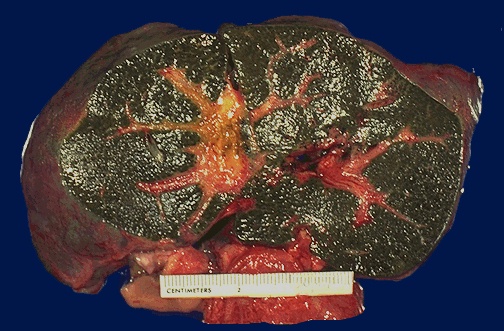

| This 3 month old child died with extrahepatic biliary atresia, a disease in which there is inflammation with stricture of hepatic or common bile ducts. This leads to marked cholestasis with intrahepatic bile duct proliferation, fibrosis, and cirrhosis. This liver was rock hard. The dark green color comes from formalin acting on bile pigments in the liver from marked cholestasis, turning bilrubin to biliverdin. |